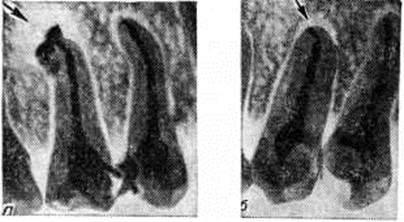

Рис. 5.

Внутриротовые рентгенограммы нижних боковых зубов при хроническом периодонтите: а — компактное вещество зубной альвеолы шестого зуба склерозировано (I), корень его (2) утолщён — гиперцементоз (признаки хронического фиброзного периодонтита); у верхушки корня пятого зуба очаг деструкции (3) костного вещества с нечёткими границами (хронический гранулирующий периодонтит), верхушка межальвеолярной перегородки (4) между пятым и шестым зубами разрушена; б — у верхушки корня пятого зуба очаг деструкции (указан стрелкой) с ровными контурами (гранулема).

Рентгенологические картина Периодонтит характеризуется следующими признаками: увеличением ширины и деформацией периодонтальной щели, разрушением или склерозом компактного вещества стенки зубной альвеолы, изменением структуры костной ткани зубной альвеолы, неровностью контуров и гиперцементозом корня зуба.

Хронический формы верхушечного Периодонтит имеют характерные особенности рентгенологическое картины. Гранулирующий Периодонтит рентгенологически проявляется как очаг деструкции костной ткани у верхушки корня зуба (рисунок 5, а). Компактное вещество стенки зубной альвеолы в этом месте разрушено. Контуры очага неровные, нечёткие. В результате резорбции цемента и дентина верхушки корня зуба контуры его становятся неровными. При гранулематозном Периодонтит (зубной гранулеме) в около верхушечной области определяется округлый очаг просветления с ровными, чёткими, иногда склерозированными контурами (рисунок 5, б). У детей и подростков зубную гранулему не следует смешивать с зоной роста зуба в области верхушки несформировавшегося корня (в ростковой зоне периодонтальная щель сохраняет равномерную ширину, компактное вещество стенки зубной альвеолы сохранено, зуб имеет широкий корневой канал).

Фиброзный Периодонтит распознается по расширению периодонтальной щели у верхушки корня зуба. Компактное вещество стенки зубной альвеолы сохранено, иногда отмечается его склероз.

Верхушка корня зуба вследствие гиперцементоза утолщена (рисунок 5, а). При обострении хронического Периодонтит рентгенологическая картина существенно не меняется.

Рис. 7.

Внутриротовые рентгенограммы верхних переднебоковых зубов при хроническом периодонтите до лечения (а) и спустя 2 года после лечения (б): а — кистогранулема (указана стрелкой) у верхушки корня второго премоляра непосредственно после пломбирования зуба; б — очаг разрешения (указан стрелкой) сократился после эндодонтического лечения.

Отдалённые результаты эндодонтического лечения верхушечных Периодонтит зависят от стерилизации и инструментальной обработки канала корня зуба, характера пломбировочного материала, клинические, форм Периодонтит, размера очага деструкции, адекватности пломбирования канала корня зуба (рисунок 7, а, б).